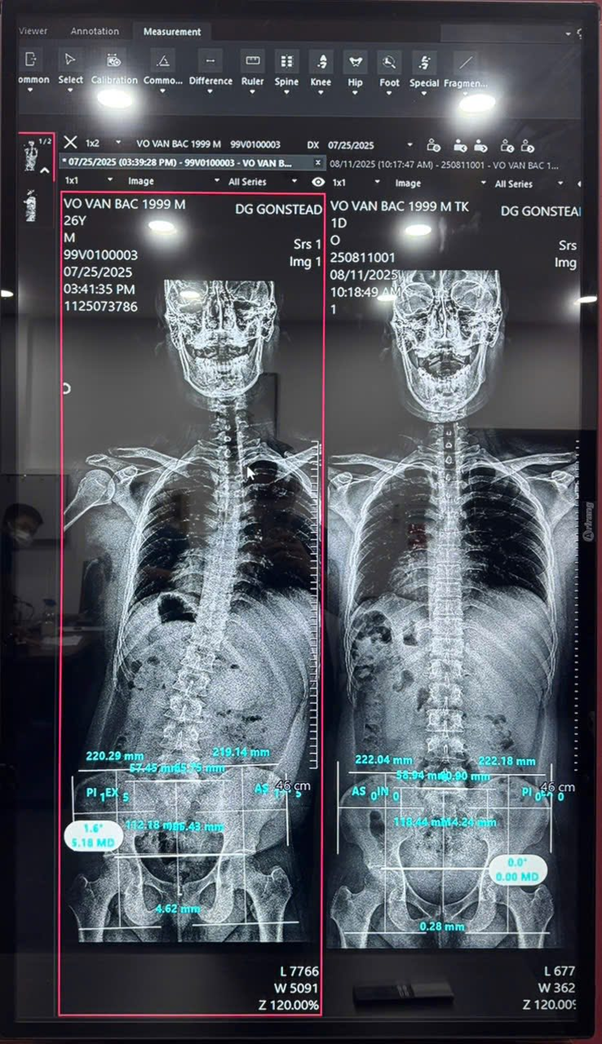

Yếu tố làm nên lợi thế cạnh tranh của DG Gonstead nằm ở sự đầu tư nghiêm túc về công nghệ. DG Gonstead đã đưa vào vận hành hệ thống chụp phim chuyên sâu kết hợp phần mềm phân tích sai lệch cấu trúc cột sống từ nước ngoài – giải pháp hiện chưa có đơn vị nào khác trong nước triển khai tương tự.

Thay vì phụ thuộc vào đánh giá cảm quan hoặc phim chụp truyền thống, phần mềm này cho phép bác sĩ phân tích độ nghiêng, độ xoay và các biến đổi vi thể trên từng đốt sống thông qua dữ liệu số hóa. Các thông số được lượng hóa giúp phác đồ điều trị mang tính cá nhân hóa cao, giảm thiểu sai số trong quá trình can thiệp. Đặc biệt, khách hàng có thể trực tiếp theo dõi hình ảnh phân tích của mình trên màn hình, từ đó hiểu rõ hơn về tình trạng sức khỏe và lộ trình phục hồi được xây dựng.